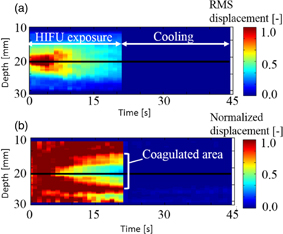

Examples of real-time LMI images are shown in Fig. 10. Maps of tissue displacement and normalized displacement are shown in Figs. 10(a) and 10(b), respectively. In this case, on-line LMI images were updated before the start of the next data acquisition. Simultaneously, the times for calculation including data transfer and displaying LMI were measured in each step; the results are shown in Fig. 11. The average and maximum calculation times were approximately 600 and 850 ms, respectively.

Standard image High-resolution imageOn the basis of these results, a prototype real-time feedback control system was constructed, and experiments using this system were conducted. The detection of the onset of coagulation is expected to be useful for exposure control in HIFU, and the real-time estimation of coagulation length in the US propagation direction is expected to be practically useful for lesion control in HIFU. Figure 12 shows LMI maps with real-time feedback control. During HIFU ablation, the tissue displacement could be measured. The results of the coagulation lengths after ablation with a constant ablation time of 30 s and feedback control based on real-time monitoring are shown in Fig. 13. The horizontal and vertical axes are the beam propagation distance and coagulation size measured with a ruler, respectively. The circles and asterisks in this figure indicate the results with constant ablation time and feedback, respectively. The dotted line indicates the targeted coagulation length. When the HIFU ablation time was constant, the coagulation lengths depended on the beam propagation distance (i.e., attenuation, and scatter). In contrast, when the HIFU ablation time was controlled by our system, the coagulation lengths were close to 10 mm. The average coagulation sizes and the average ablation times are shown in Table II. The size of the error for the short beam propagation distance (L = 10 mm) was reduced to 10% from 22%. The size of the error for the long beam propagation distance (L = 30 mm) was reduced to 14% from 35%. The standard deviations of the entire data set (calculated using the total of L = 10 and 30 mm) with constant time ablation and feedback control were 2.98 and 1.37, respectively. This result demonstrated that our prototype feedback control system could reduce the variation in coagulation size. In addition, the average ablation times for the short and long beam propagation distances were 25.2 and 35.2 s, respectively.

Fig. 12. LMI maps of real-time feedback control experiments (L = 30 mm, 20 °C, feedback control ablation).